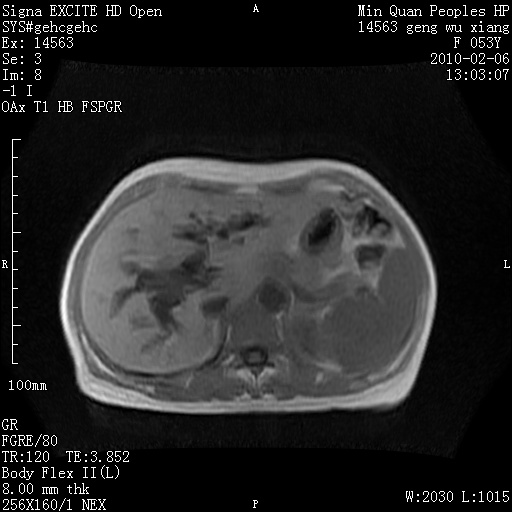

标题: MRI2762:胆道梗阻原因?

f,53y,全身黄染多日。

高位胆道梗阻 胆管癌可能性大

支持 高位胆道梗阻 胆管癌可能性大。